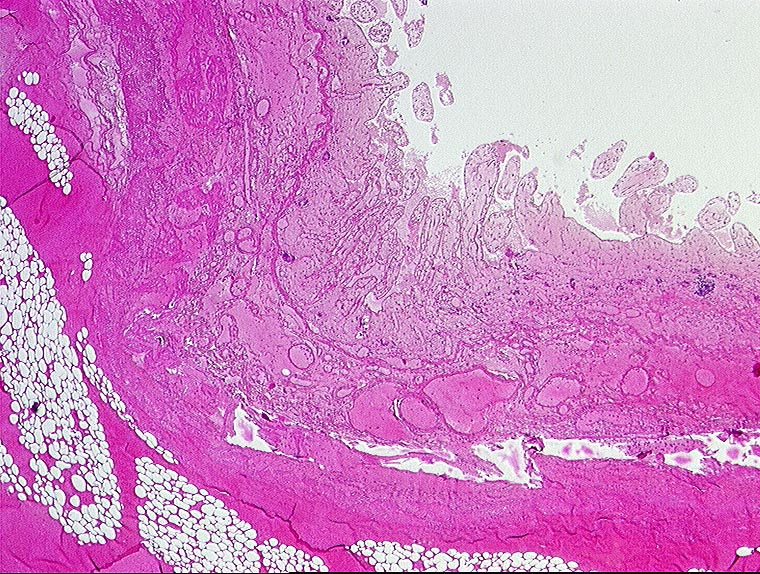

AP/ Mesenterialinfarkt

Mesenterialinfarkt

vaskulär / Durchblutungsstörung

Darm, Anus

Dünndarm

Makroskopie